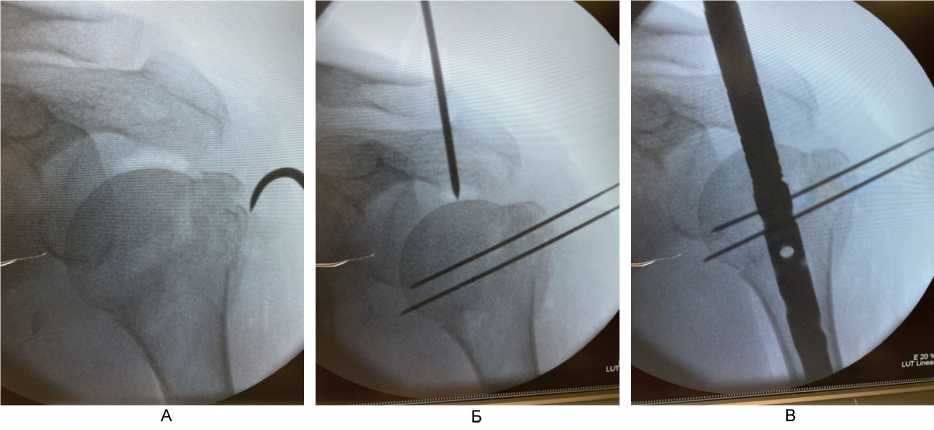

При переломах типа А и В по АО с 2020 г. по настоящее время использовали методику интрамедуллярного остеосинтеза из доступов по типу проколов (до 1 см) с применением непрямой репозиции с помощью спиц-джойстиков (рис. 4), время опреации – 31 мин.

Рис. 4. Непрямая репозиция под рентгенологическим контролем (ЭОП) с помощью спиц-джойстиков при переломах типа А и В по АО. А – установка толстой спицы-джойстика в проксимальный отломок; Б – репозиция варусного отклонения проксимального отломка; В – выбор точки для вскрытия интрамедуллярного канала плечевой кости под имплантат; Г – контроль положения направителя для вскрытия интрамедуллярного канала плечевой кости

При переломах типа В по АО с выраженным смещением большого бугорка плечевой кости использовали минимально инвазивную методику остеосинтеза. Выполняли доступ по наружной поверхности в области плечевого сустава длиной 3–4 см в проекции большого бугорка, с помощью однозубого крючка производили репозицию большого бугорка и временную фиксацию его 2 спицами Киршнера (рис. 5). Спицы вводили таким образом, чтобы в ходе операции предотвратить возможные конфликты в процессе вскрытия, рассверливания костномозгового канала и введения штифта. После введения штифта большой бугорок фиксировали блокирующим винтом (дополнительно по необходимости применяли методику «винт в винте» [21]), при оскольчатом переломе большого бугорка для более надежной фиксации мелкого фрагмента дополнительно подшивали его через специальное отверстие в блокирующем винте, далее спицы удаляли. Блокирующие винты вводили по направителям из проколов длиной 1 см. Интраоперационная кровопотеря составляла не более 50 мл.

Рис. 5. Этапы репозиции отломков и установки интрамедуллярного штифта при переломах типа Б по АО. А – прошивание сухожилий манжеты ротаторов с костными отломками; Б – репозиция и временная фиксация отломков тонкими спицами Киршнера, установка направляющего устройства для вскрытия интрамедуллярного канала плечевой кости; В – установка интрамедуллярного штифта в плечевую кость